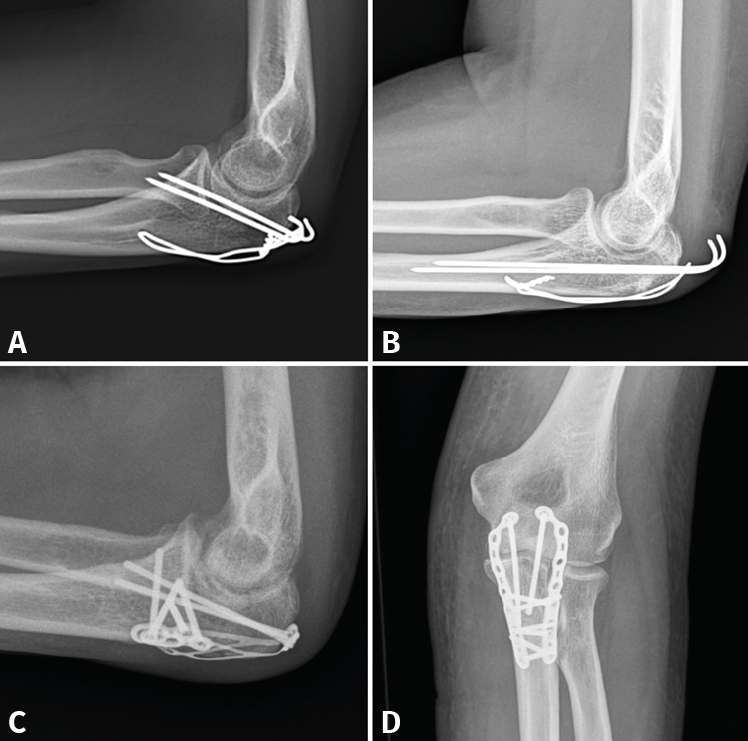

Figura 8. Ejemplos de fracturas de olécranon en 2 partes (tipo 2A) fijadas con obenque (A y B) y fracturas de tipo 2B fijadas con distintos diseños de placas (C y D).

- 2A/2B: son las más frecuentes. La técnica de elección en las fracturas simples en 2 partes es un cerclaje de alambre (obenque) sobre 2 agujas de Kirschner (AK) ancladas a la cortical anterior o colocadas intramedulares. En el primer caso, tenemos riesgo de lesionar las estructuras neurovasculares volares, por lo que no deben sobresalir más de 10 mm; en el segundo caso, el riesgo de que migren proximalmente es mayor(34,35). Se pensó que con este montaje las fuerzas de tensión se transforman en fuerzas de compresión, pero varios estudios realizados no han podido demostrar este principio(36). En las conminutas 2B se recomienda fijación con placa, precisamente para evitar la excesiva comprensión de la cavidad sigmoidea que llevaría a una artrosis precoz. Se recomiendan las placas premoldeadas LCP (locking compression plate). Su efectividad y seguridad están de sobra probadas; sin embargo, al ir en una posición dorsal y ser el cúbito subcutáneo, pueden producir irritación de los tejidos blandos y con cierta frecuencia hay que retirarlas. Aun así, el índice de retirada es mucho mayor en los cerclajes, que puede llegar hasta el 90%(37,38). La alternativa es usar 2 placas laterales de bajo perfil colocadas a ambos lados de la cresta, una medial y otra lateral, que además tienen la ventaja de permitir una fijación bicortical de los fragmentos más proximales. En cualquier caso, los estudios demuestran que ambos métodos tienen buenos resultados y no existen diferencias a corto plazo. Últimamente, se están publicando modificaciones a la técnica clásica del obenque, usando una sutura trenzada de alta resistencia en lugar de alambre(39). En este caso solo tendríamos que retirar las AK y este es un proceso mucho menos invasivo (Figura 8).

- 3A, IB, 2B, 3B: siempre que exista conminución o inestabilidad, el tratamiento de elección será la osteosíntesis con una placa de ángulo fijo LCP, con tornillos de bloqueo adaptados anatómicamente que permiten reducir casi todos los fragmentos.